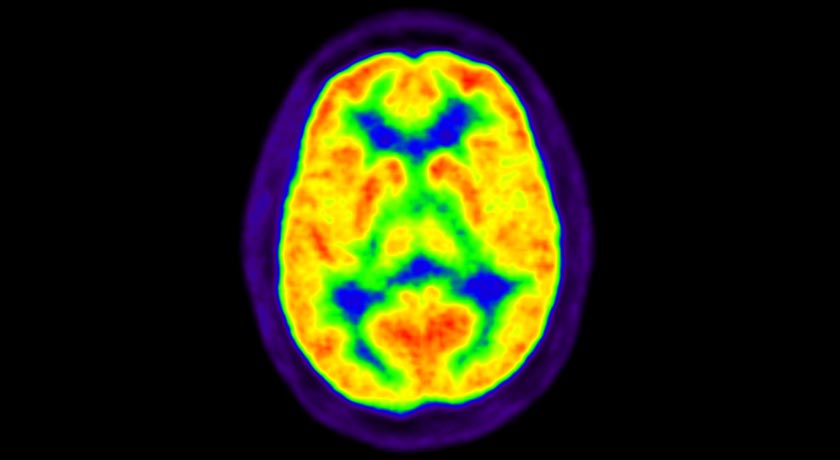

NUCLEAR BRAIN In 1965, researchers developed a way to track radioactive carbon in the body. Today, positron emission tomography (PET) scans work by the same method to diagnose diseases.

TRIUMF Lab/Flickr (CC BY-NC-SA 2.0)